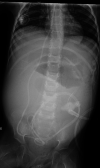

A ventriculoperitoneal (VP) shunt is a commonly used mechanical device indicated for congenital and acquired hydrocephalus in children. Although VP shunt failure is not uncommon, the symptomatology and cause of failure can vary. In this case, we describe intestinal obstruction in a three-year-old Caucasian female with a history of Pilomyxoid Astrocytoma and VP shunt placement for the management of hydrocephalus. Surgical exploration revealed ischemia of the terminal ileum secondary to VP shunt tubing-induced adhesions requiring bowel resection. A secondary VP shunt infection due to Enterococcus faecalis was also noted. Our case highlights a unique presentation of intestinal obstruction and infection that should serve to increase provider suspicion when evaluating patients presenting with abdominal distention and pain with presence of a VP shunt.